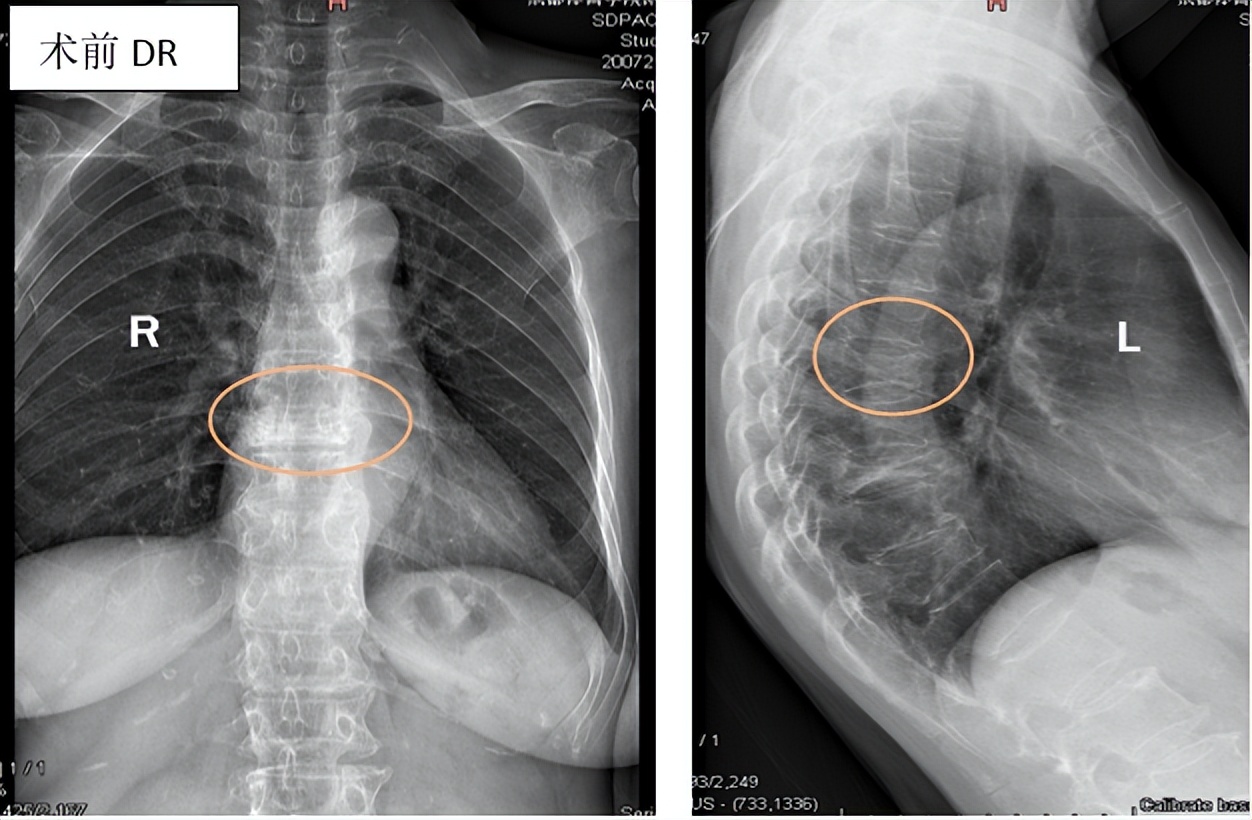

影像学检查

常用的有X线、CT、MRI、骨扫描。